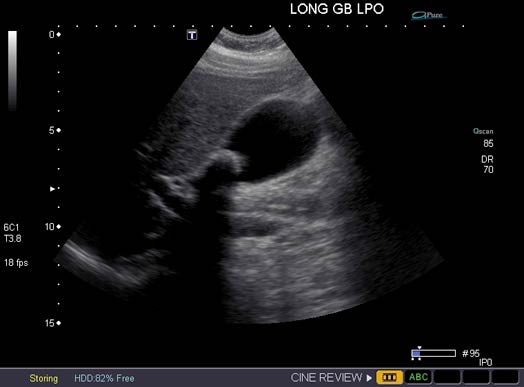

An ultrasound image of the right upper abdomen showing a large stone within the gallbladder.

Note: Images are shown for illustrative purposes. Do not attempt to draw conclusions or make diagnoses by comparing these images to other medical images, particularly your own. Only qualified physicians should interpret images; the radiologist is the physician expert trained in medical imaging.